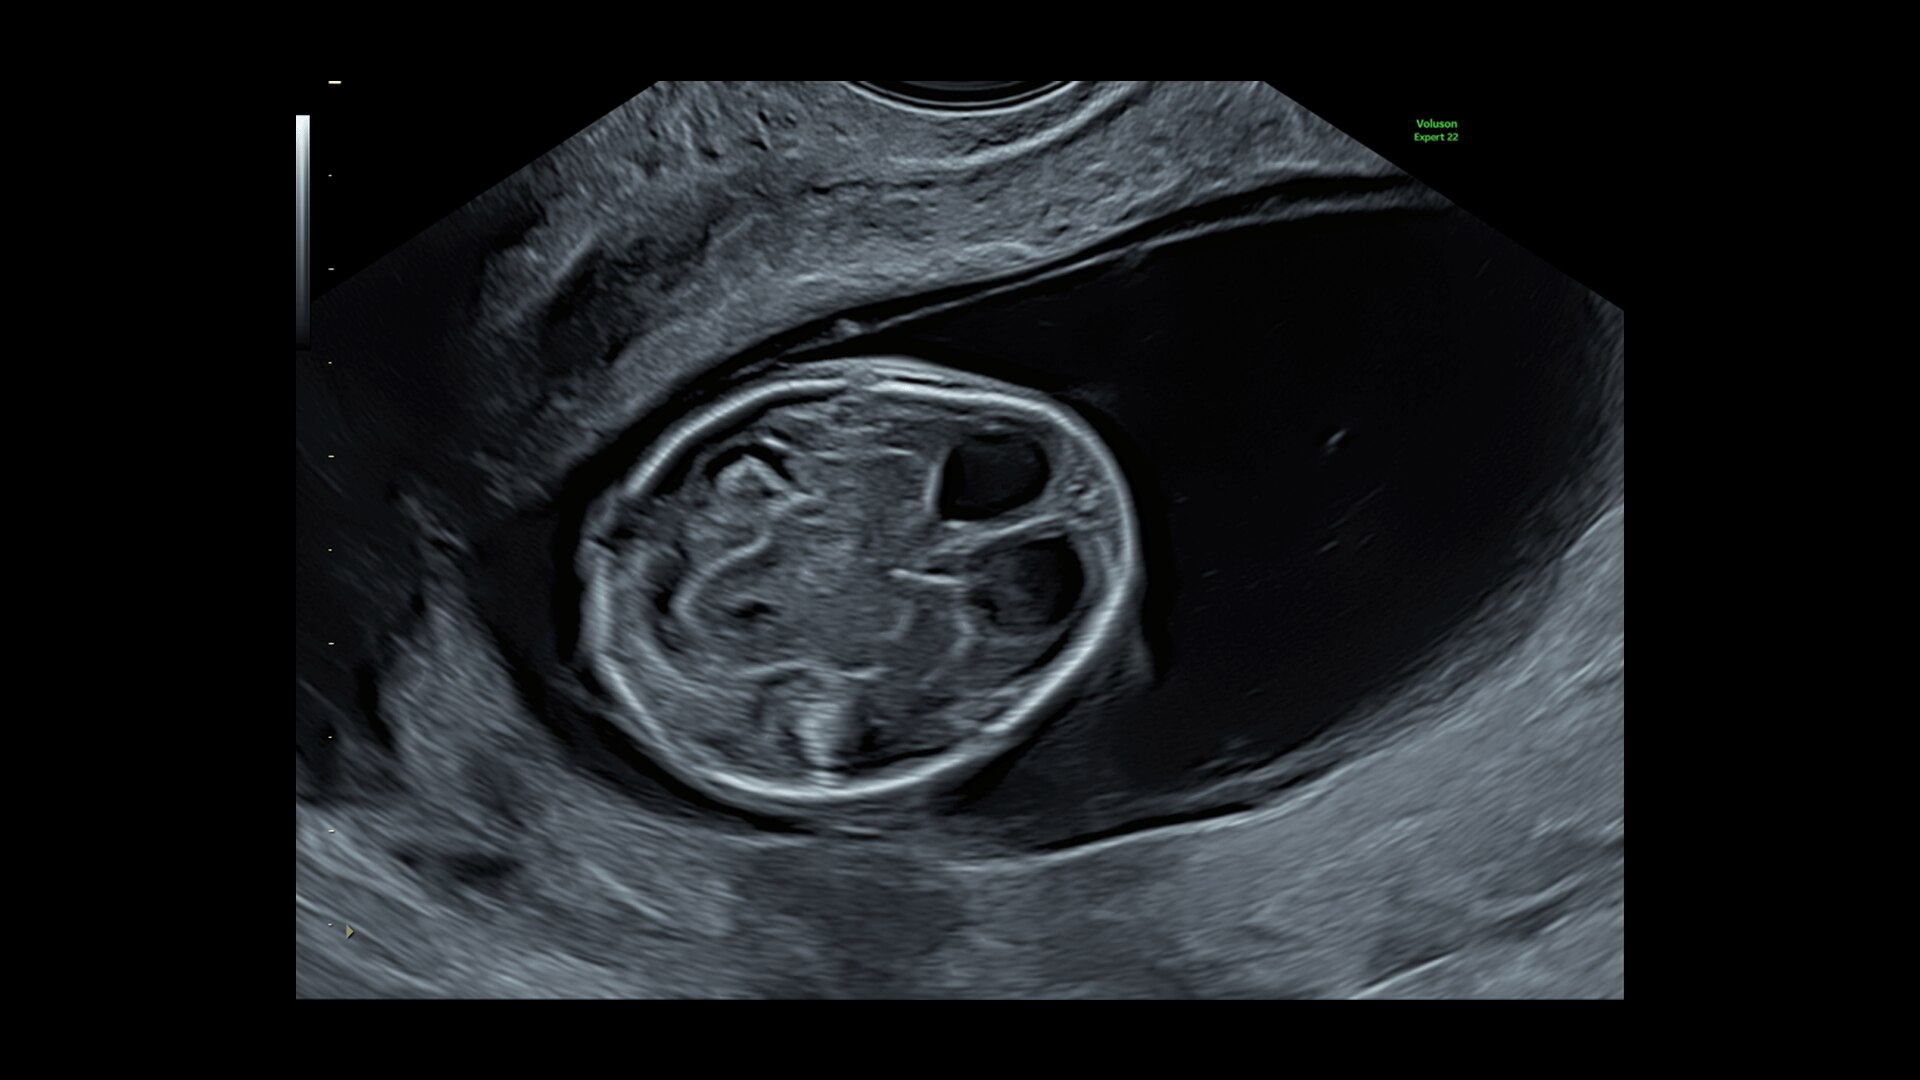

FETAL HEART EVALUATION

Get to the Heart of the Matter

Identifying fetal cardiac abnormalities earlier means you can intervene sooner, plan for delivery, and potentially improve outcomes. The Voluson Expert 22 provides a full solution of progressive tools, to help distinguish the tiniest structures with stunning clarity to provide patient answers faster.